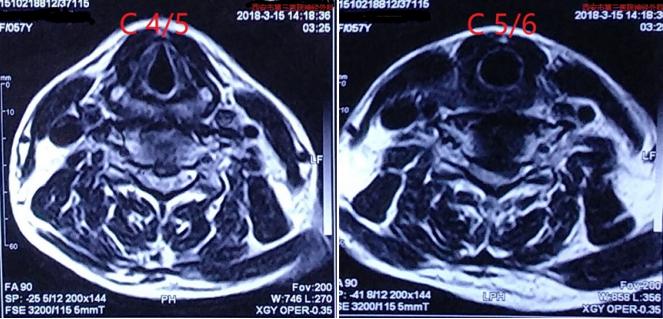

术后颈椎MRI复查

矢状位颈椎MRI:颈4/5、5/6脊髓前方压迫解除,椎管宽度恢复

轴位颈椎MRI提示颈4/5、5/6突出椎间盘切除,脊髓受压解除